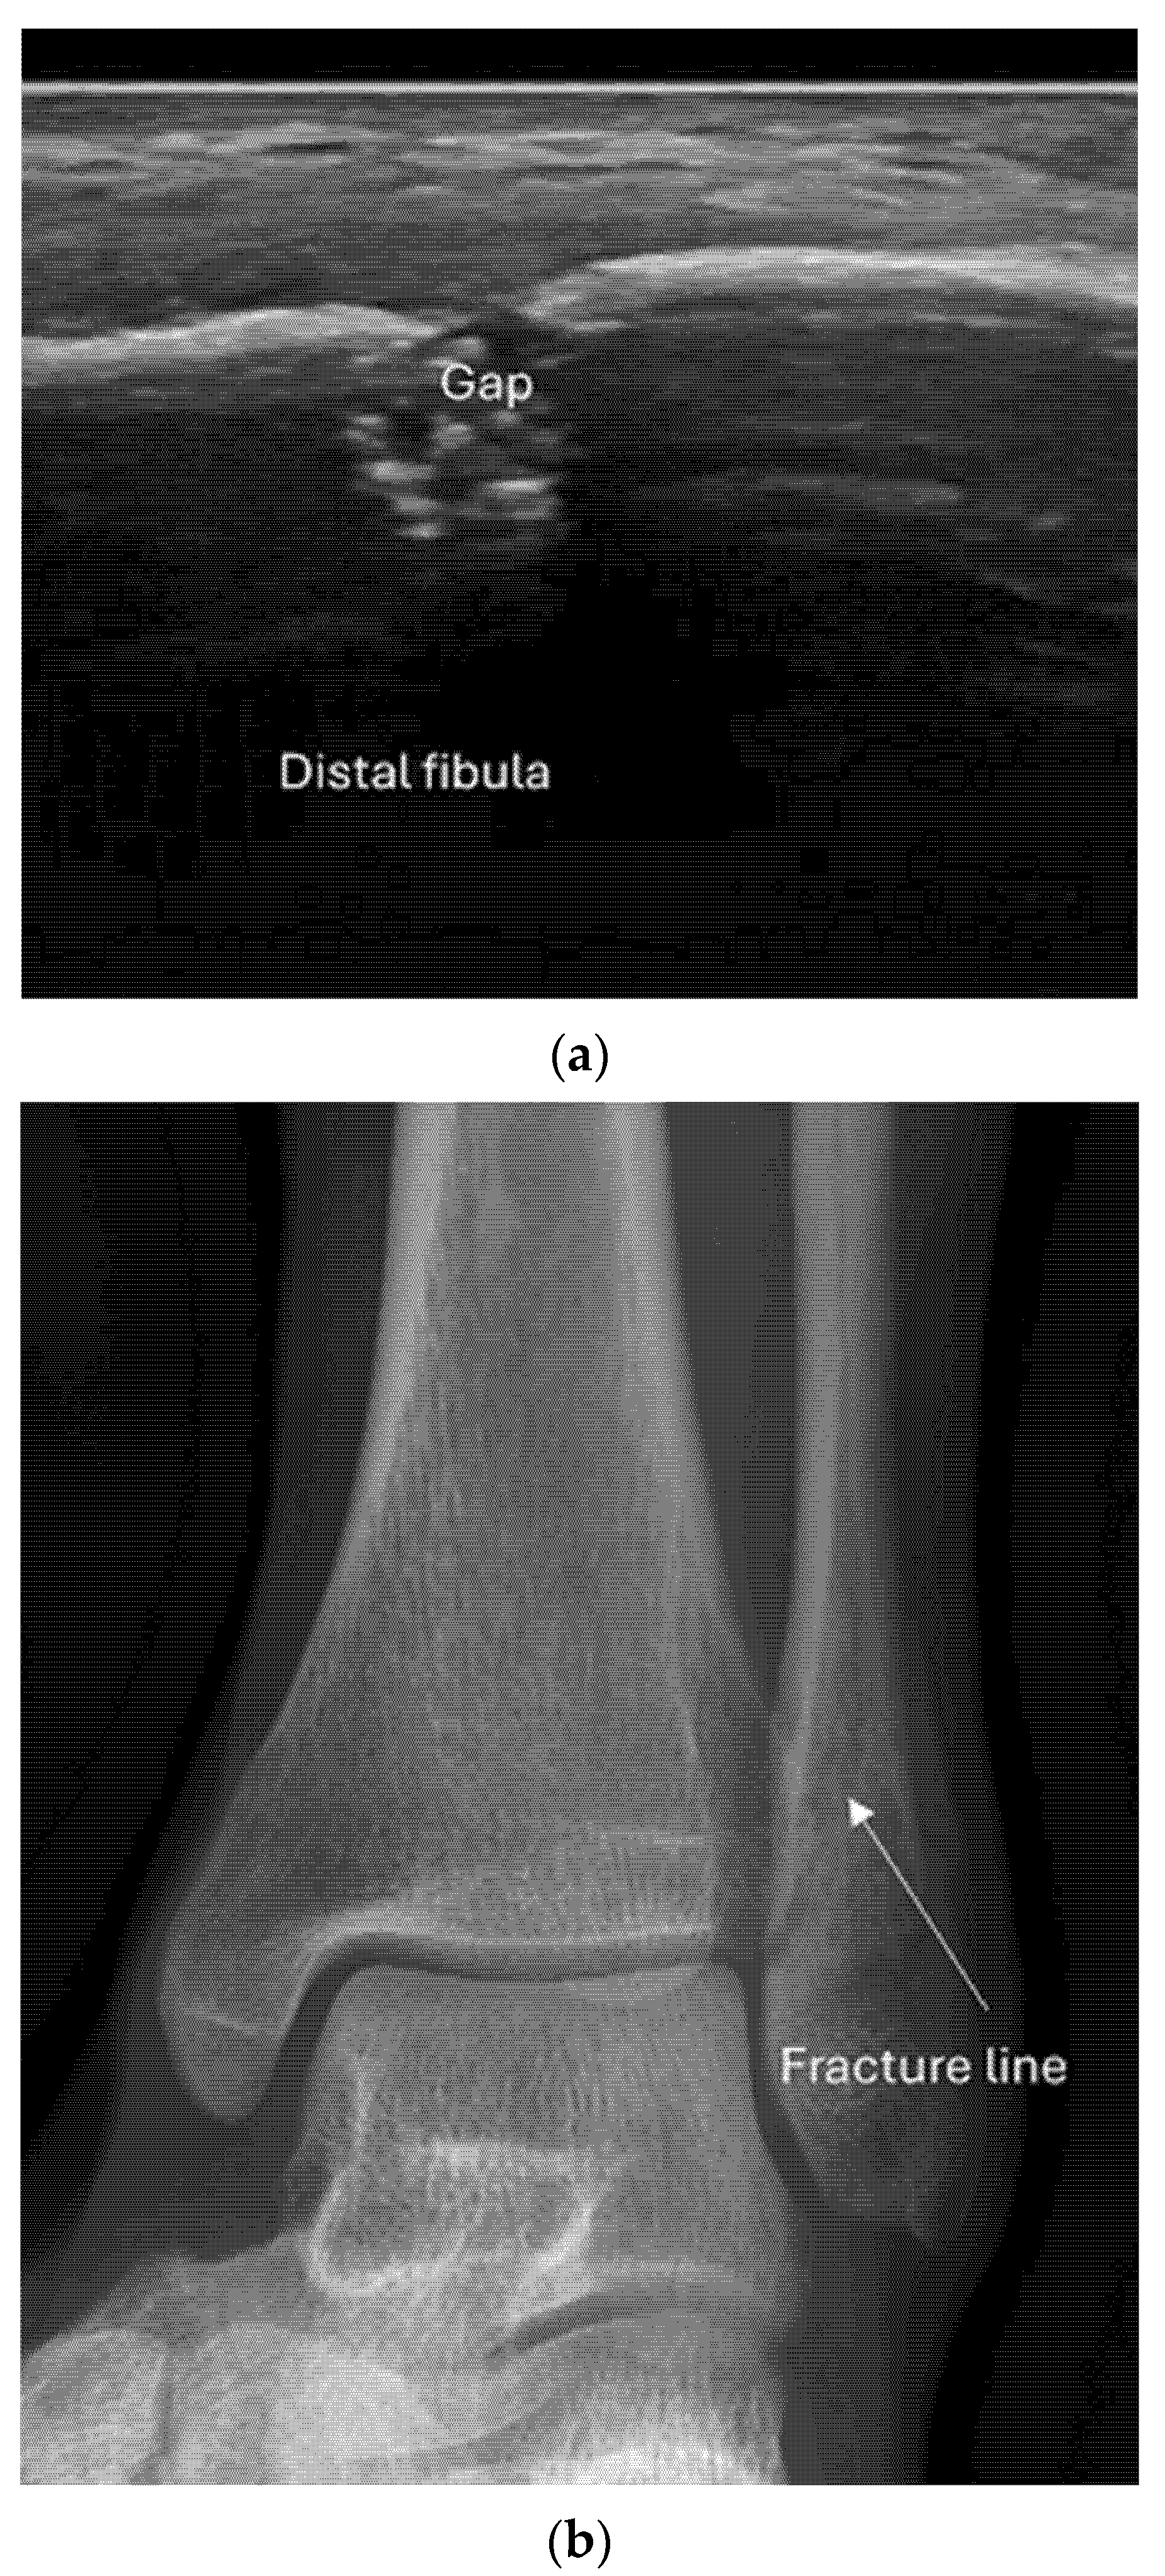

4.2. Sonoanatomy of Fractures [Figure 5, Figure 6, Figure 7 and Figure 8]

- Irregularity, interruption, or gaps in the cortical line: the cortical bone normally appears as a continuous, bright echogenic line, which is interrupted or irregular in the presence of a fracture.

- Reverberation artifacts within or adjacent to the fracture gap (also known as the “chimney sign”): these repetitive echoes are caused by ultrasound waves reflecting off the fracture surfaces.

8.2. Screening of Patients with Suspicion of Occult and Stress Fractures (Figure 11 and Figure 12)

- Recommendation 2: Given the promising but limited evidence, ultrasound should be considered a first-line imaging tool for suspected occult fractures, except in the pelvis and vertebral column.

- Recommendation 3: Ultrasound should be used as first-line imaging for suspected stress fractures, with follow-up X-ray if evidence of a stress fracture is identified. Exceptions include pelvic and vertebral column fractures.